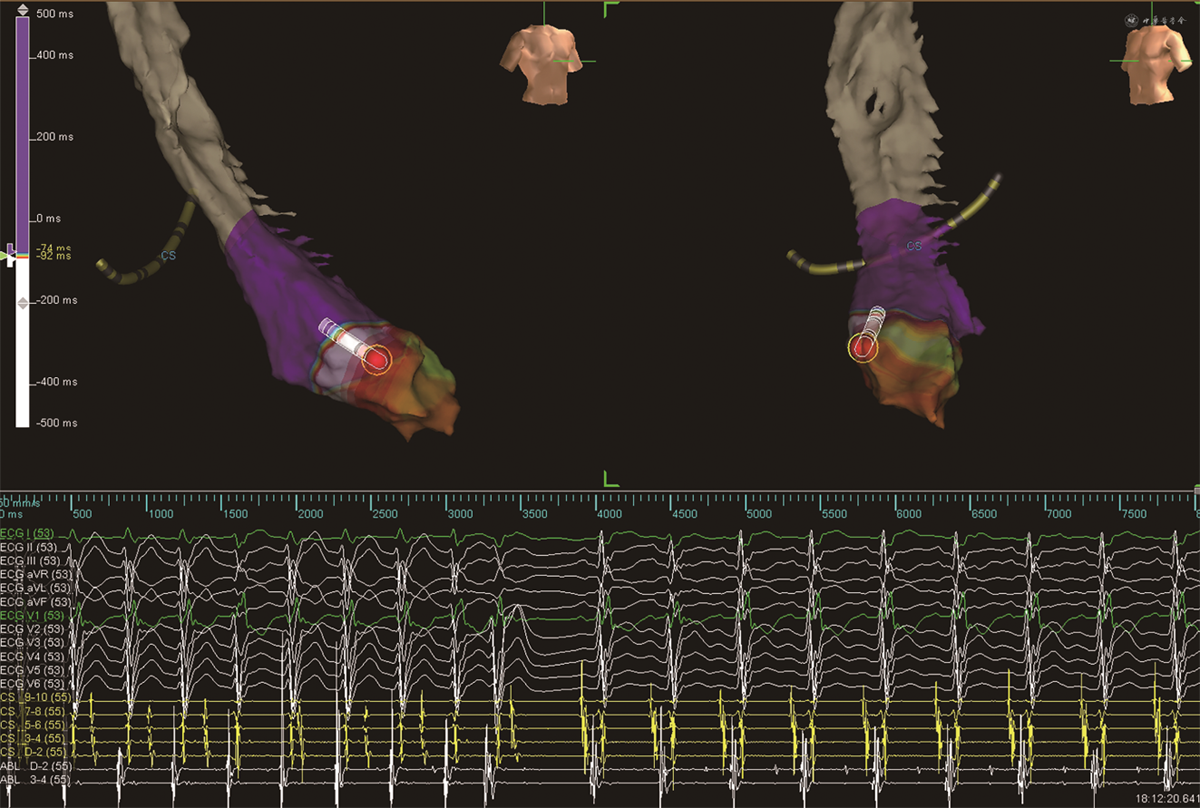

出院后7个月时患者心悸再发,症状同前,复查心电图为室速(图5A),口服维拉帕米80 mg后维持窦性心律(图5B)。为行射频消融术收入院。复查超声心动图示:LAD 24 mm,LVEDD 48 mm,LVEF 74%。复查NT-proBNP 19.92 pg/mL,hs-cTnT 0.010 ng/mL。行电生理标测为左心室间隔偏前室速,频率170bpm,三维标测下送大头电极于左心室间隔偏心尖处消融成功(图6)。术后当天心电图为RBBB(图5C),第二天RBBB消失(图5D),但静息时心率90次/分,出院时继续口服美托洛尔治疗,停用沙库巴曲缬沙坦。